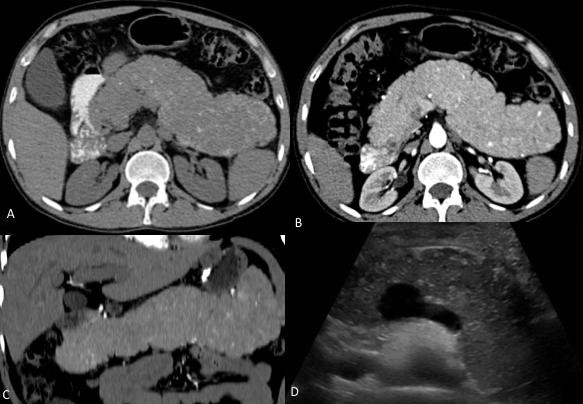

Por ultrasonido se demostró parénquima hepático normal y páncreas con aumento de volumen y ecogenicidad heterogénea. Por tomografía multifásica el páncreas mostró aumento de volumen en su totalidad, precontraste densidad heterogénea con zonas nodulares hiperdensas y calcificaciones, con atenuación promedio de 45UH, realce arterial con atenuación de 86UH, portal 112UH y disminución en fase venosa a 100UH. Además se observó colapso de la porción distal de la vena esplénica y circulación colateral en hilio esplénico, fondo gástrico y periesofágica (Fig. 1 y 2). La medición de gradientes hepáticos y angiografía de tronco celíaco con presión de vena suprahepática libre 12mmHg, presión enclavada 14mmHg, gradiente de 2mmHg, sin evidencia de shunts intrapancreáticos, hallazgos consistentes con hipertensión portal postsinusoidal (Fig. 2).